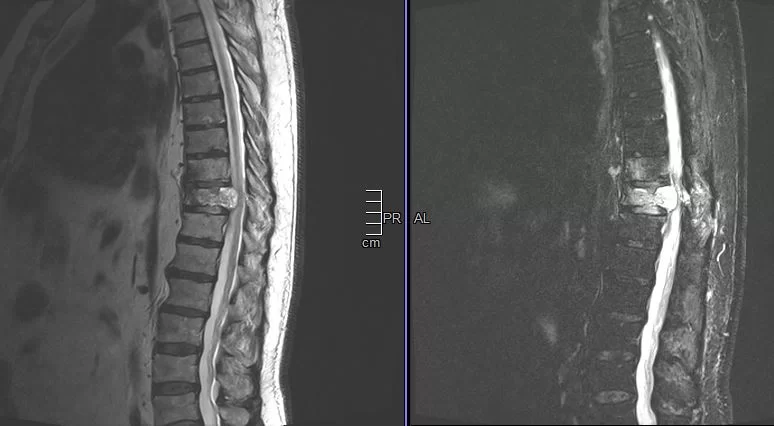

Νεαρή ασθενής 17 ετών με εκτεταμένη συριγγομυελία από την αυχενοπρομηκική συμβολή έως το τελικό τμήμα του νωτιαίου μυελού, λόγω συνδρόμου Chiari. Κλινικά αιμωδίες (μουδιάσματα) άνω

Σύνδρομο Chiari – Συριγγομυελία